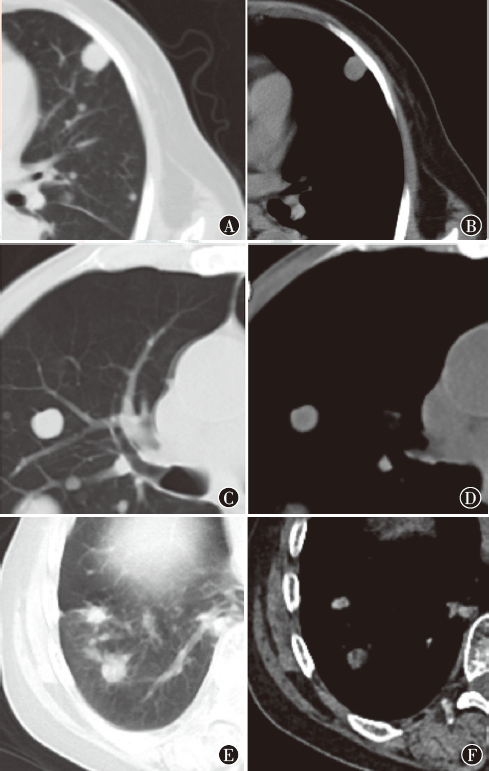

摘要:

Objective To distinguish lung metastases of different origin by constructing a classification model according to CT radiomics features. Methods A total of 226 patients with lung metastases of gastric cancer, breast cancer and kidney cancer attending Chongqing Red Cross Hospital from January 2015 to July 2020, with a total of 402 metastases, were randomly divided into a training cohort (training set, 136 patients, 280 metastases) and a validation cohort (validation set, 90 patients, 122 metastases) by the hold-out method. In addition, 68 patients with lung metastases (138 lung metastases in total) attending Chongqing Red Cross Hospital from August 2020 to April 2022 were matched as an external test cohort (test set). Region of interest segmentation was performed by two experienced radiologists independently and manually without clinical information to construct the model by using LASSO screening for the best radiomic features. Support vector machine (SVM) and random forest (RF) were selected to build dichotomous and trichotomous models respectively. The receiver operating characteristic curve was used to evaluate the classification efficiency of both models. Results There were no statistically significant differences in age (t=-0.06, P=0.534), gender (χ2<0.01, P=0.961) and number of lung metastases (χ2=0.71, P=0.703) between the validation and test sets. A total of 792 radiomic features were extracted, 703 of which had good agreement (intraclass correlation coefficient≥0.75), while 89 features being excluded for having poor agreement (intraclass correlation coefficient<0.75). The dichotomous model (SVM) screened 28 (lung metastases from gastric cancer vs. lung metastases from breast cancer), 25 (lung metastases from gastric cancer vs. lung metastases from kidney cancer) and 34 (lung metastases from kidney cancer vs. lung metastases from breast cancer) features, respectively; the trichotomous model (RF) screened 20 features (three types of lung metastases), in which Short Run Emphasis and Inverse Variance were significantly higher in lung metastases from kidney cancer than in the other two types, correlation was higher in lung metastases from gastric cancer than in the other two types, and there was no significant difference in the sphericity of the three lung metastases. For the dichotomous model, in the validation set, the area under the curve (AUC) of the 28 features selected to distinguish gastric cancer lung metastases from breast cancer lung metastases was 0.81, the AUC of the 25 features distinguishing gastric cancer lung metastases from kidney cancer lung metastases was 0.86, and the AUC of the 34 features distinguishing kidney cancer lung metastases from breast cancer lung metastases was 0.92, and the AUCs of the test set were 0.80, 0.79 and 0.86 respectively. For the trichotomous model, the AUC for predicting lung metastases from gastric cancer, breast cancer and kidney cancer in the validation set were 0.85, 0.82 and 0.91 respectively, and both macroscopic and microscopic AUC were 0.85; In the test set, the AUC for predicting lung metastases from gastric cancer, breast cancer, and kidney cancer were 0.77, 0.86 and 0.84 respectively, and both macroscopic and microscopic AUC were 0.81. Conclusion The SVM and RF models based on CT radiomic features are helpful in distinguishing lung metastases derived from gastric cancer, breast cancer and kidney cancer.